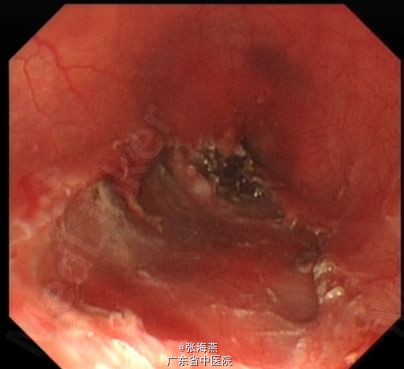

诊断:食管下段平滑肌瘤 处理:排除禁忌症后,于2013-7-23在气管插管全麻下行食管肿物ESD术,术中所见:食管距门齿35cm见隆起性肿物,大小约2.5cm×2cm,表面光滑;切除肿物拿出体外测量,大小约5.3cm×2.5cm×1cm。术程顺利,术后予静滴明可欣抗感染,泮托拉唑静滴抑酸护胃,铝镁加混悬液口服保护胃粘膜,以及补液支持治疗。术后病理提示:(食管肿物)平滑肌瘤;免疫组化结果:Vimentin(+),SMA(+),Desmin(+),CD117(—),CD34(—),Ki67(<1%+)。5天后患者病情稳定出院。